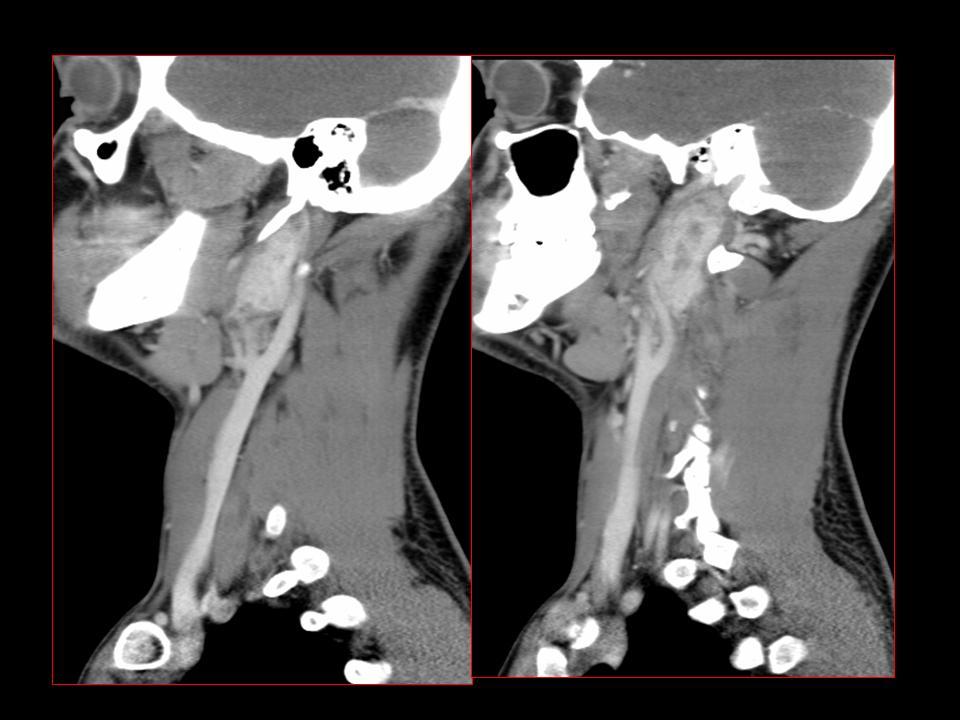

CT

High-density bone deposition within the membranous labyrinth:

mild disease: hazy increase in density within fluid spaces of the membranous labyrinth

moderate disease: focal areas of bony encroachment on fluid spaces of the membranous labyrinth

severe disease: membranous labyrinth completely obliterated by bone replacing fluid spaces

The term otosclerosis is somewhat of a misnomer. Much of the clinical course is characterised by lucent rather than sclerotic bony changes and hence it is more appropriately known as otospongiosis which is a term preferred by many head and neck radiologists.